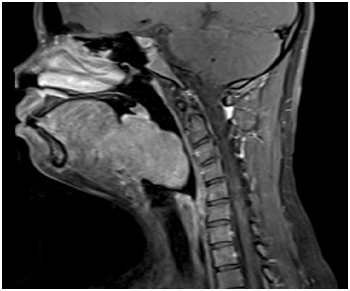

She underwent elective tracheostomy to secure the airway, followed by embolization of the feeding vessels (sublingual arteries) before proceeding to transoral endoscopic excision of the base of tongue mass (Figure 2) using blade and diathermy. She was able to tolerate oral intake at day four post-operatively. She also had a good airway after the operation and her tracheostomy was successfully decannulated four weeks after the operation with return of normal speech. Histological examination confirmed the mass to be an ectopic thyroid with adenomatous proliferation. She was hypothyroid post-operatively and was subsequently started on Thyroxine.

Figure 2 Intra-operative view for Case 1.